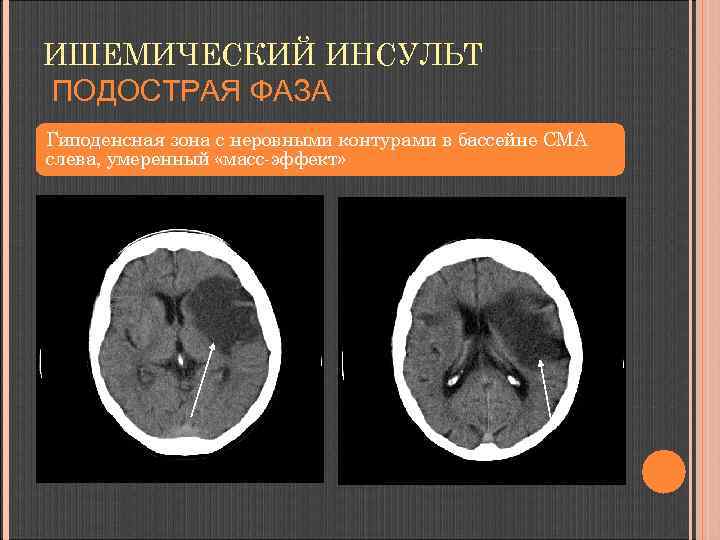

ИШЕМИЧЕСКИЙ ИНСУЛЬТ ПОДОСТРАЯ ФАЗА 3 -8 сутки (нарастает цитотоксический и вазогенный отек, распад зоны некроза). ГИПОДЕНСНАЯ зона, распространяющаяся на белое и серое вещество в типичном артериальном бассейне; нарастает «масс-эффект» . в первые 4 -6 суток - признаки геморрагического пропитывания – участки повышения плотности в подкорковых узлах и по ходу извилин – 15 -20%

ИШЕМИЧЕСКИЙ ИНСУЛЬТ ПОДОСТРАЯ ФАЗА Гиподенсная зона с неровными контурами в бассейне СМА слева, умеренный «масс-эффект»